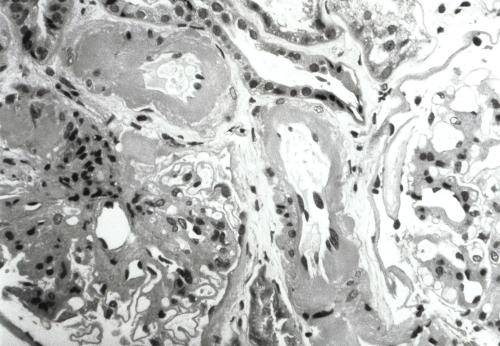

She presented again two months later with a pulmonary exacerbation, having a creatinine level of 0.22 mmol/L. Ceftazidime monotherapy and intravenous fluids were began. A renal biopsy demonstrated severe, diffuse glomerulosclerosis with arteriolar vasculopathy (Figure 1).

Figure 1. Renal biopsy. This demonstrates glomeruli with a global increase in the mesangial matrix. Arterioles demonstrate marked circumferential hyalinization with variable mural thickening and luminal narrowing. |

There were areas of attenuated tubular epithelial cells, consistent with mild tubular injury. There was no evidence of amyloidosis on standard stains using light microscopy and electronic microscopy. Immuno-fluorescence was negative. Lisinopril was begun and diabetic control was re-assessed. Lisinopril was discontinued due to severe symptomatic postural hypotension. Renal protein excretion persisted in the range 400-700 mg/24h. There was no clinical evidence of diabetic neuropathy. Retinal examination demonstrated proliferative diabetic retinopathy in her left eye, requiring laser therapy. The right eye demonstrated pre-proliferative changes.